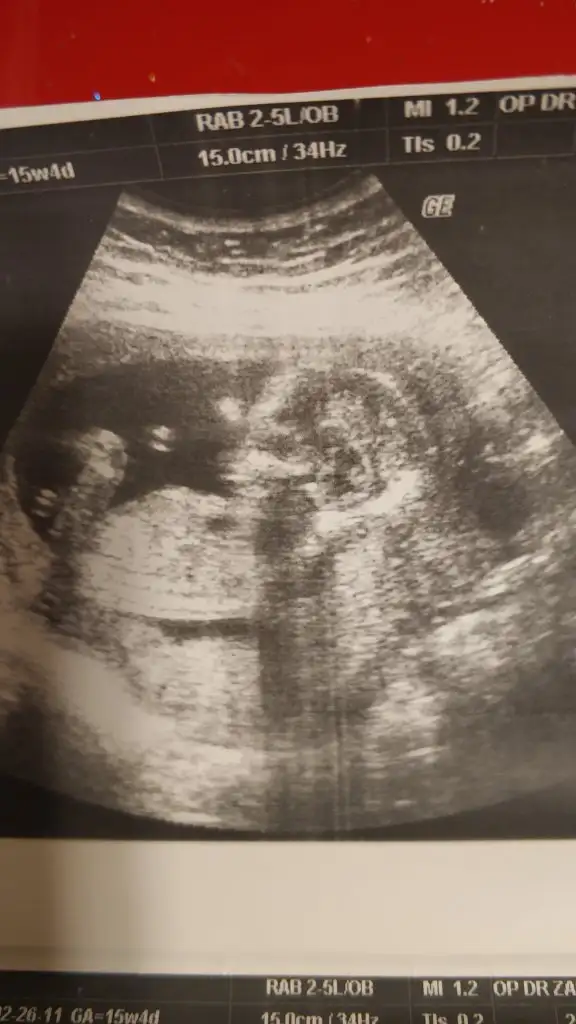

Kız gibiIkra meyra tekrar usg paylaşın demiştiniz sat a göre 12+1 ultrasona göre 12+6 çıktık ❤Pazartesi tekrar gideceğim ama bunu da atmak istedim belki bir tahmin olur

![]()

11 12 13 haftalar nub için uygun şimdilik sanki erkek gibi gibi dediğimiz usgleri paylaşırmısınızIkra meyra bir bakarmısın canım

Şuan 19 haftalık kordon dolandığı için göremedi doktor cinsiyeti11 12 13 haftalar nub için uygun şimdilik sanki erkek gibi gibi dediğimiz usgleri paylaşırmısınız